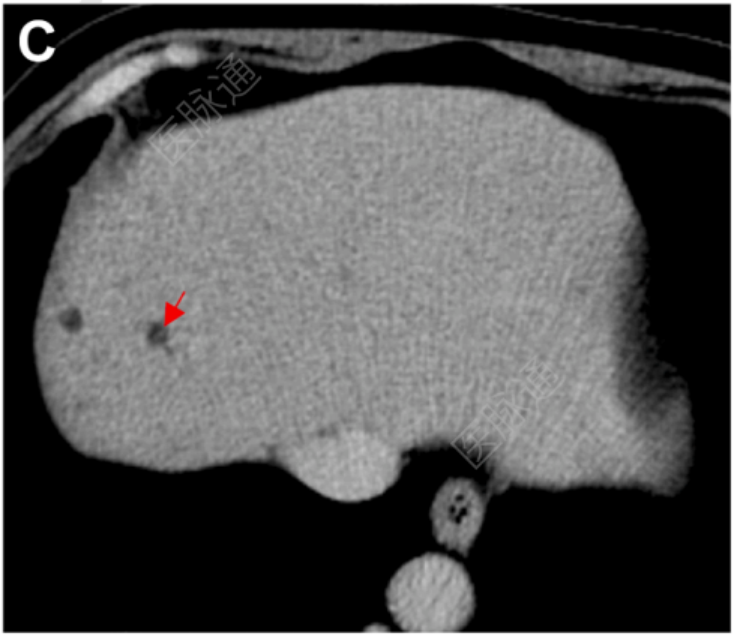

增强腹部计算机断层扫描(CT)显示,静脉期肝内多发低密度病灶,伴中央点状强化(图C)。